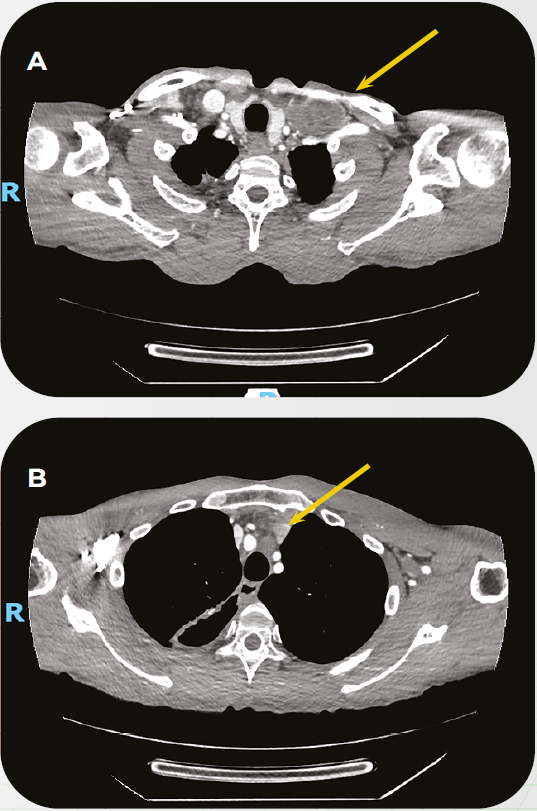

Caso Clínico: Tratamento de paciente com Câncer de Esôfago avançado com PPC>10 em 1L

O caso clínico compartilhado peo oncologista Dr. Rodrigo Guedes, constam detalhes sobre o tratamento de paciente com Câncer de Esôfago avançado com PPC>10 em primeira linha.